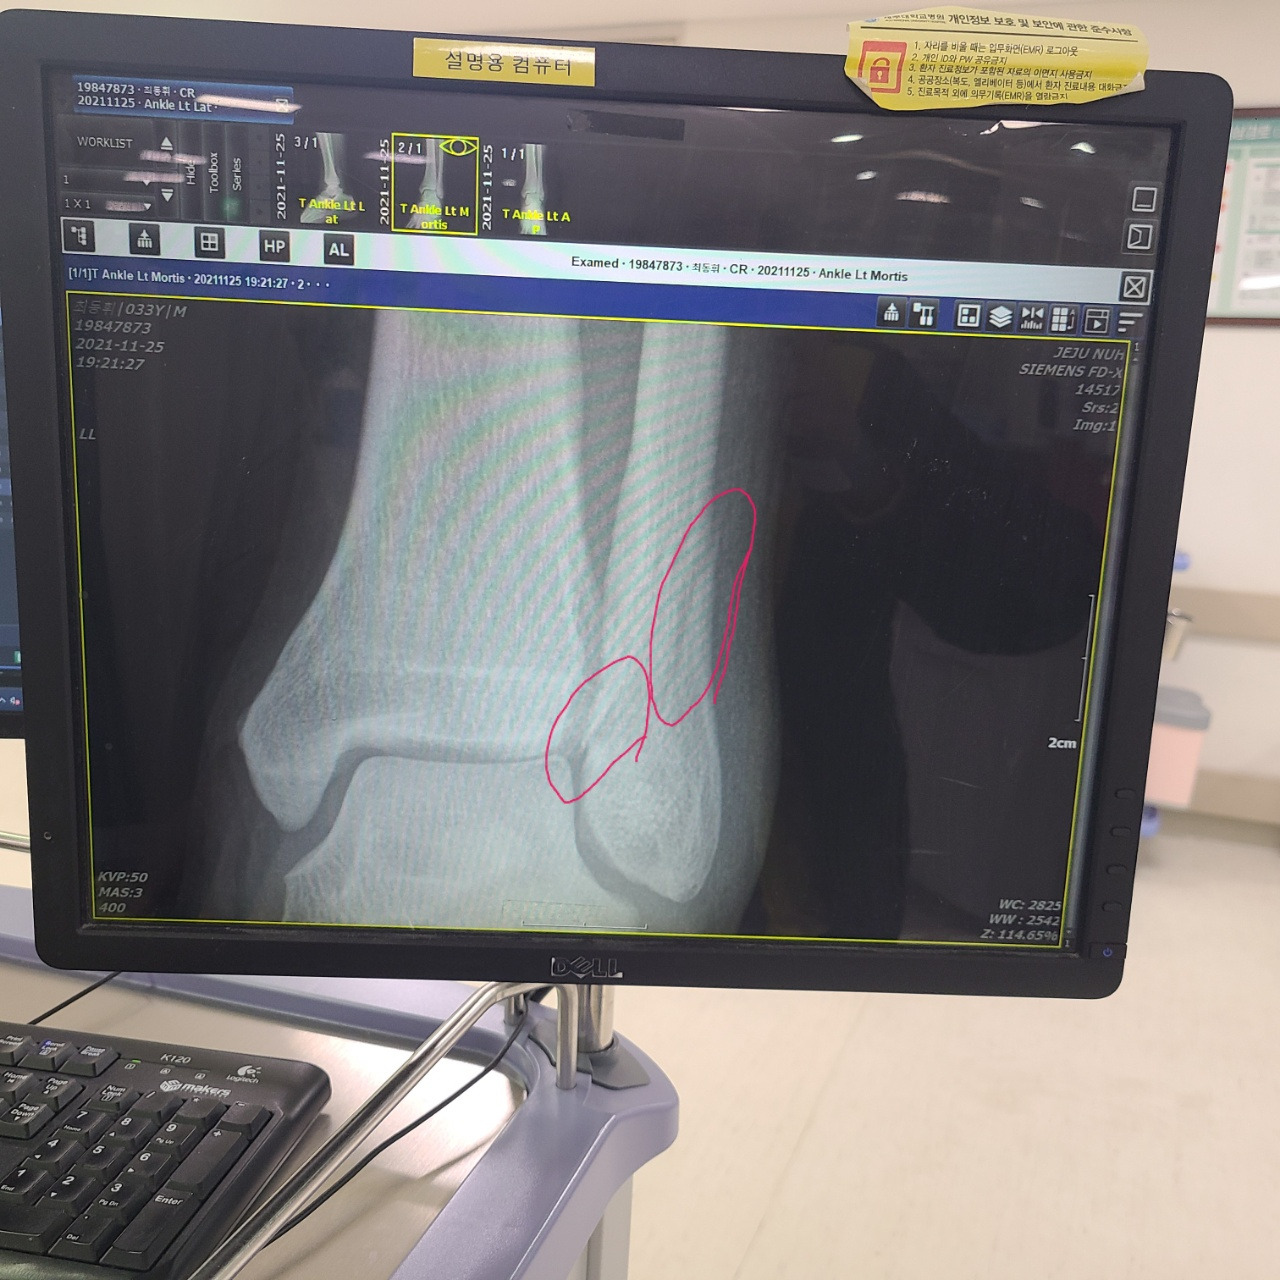

서울로 올라와서 받은 초기 진료 엑스레이 사진

뼈가 부러져서 수술을 당장 해야 한다고 했다.

조금만 더 늦었으면 뼈가 쪼개질 뻔했다고 했다. 뼈가 쫙하고 쪼개지면 파편부터 해서 살 밖으로 뼈가 튀어나올 수도 있었고, 큰 수술이 이어질뻔했다고 했다. 심각하게는 장애로 이어질 수 있다는 무서운 말을 의사는 내뱉었다.